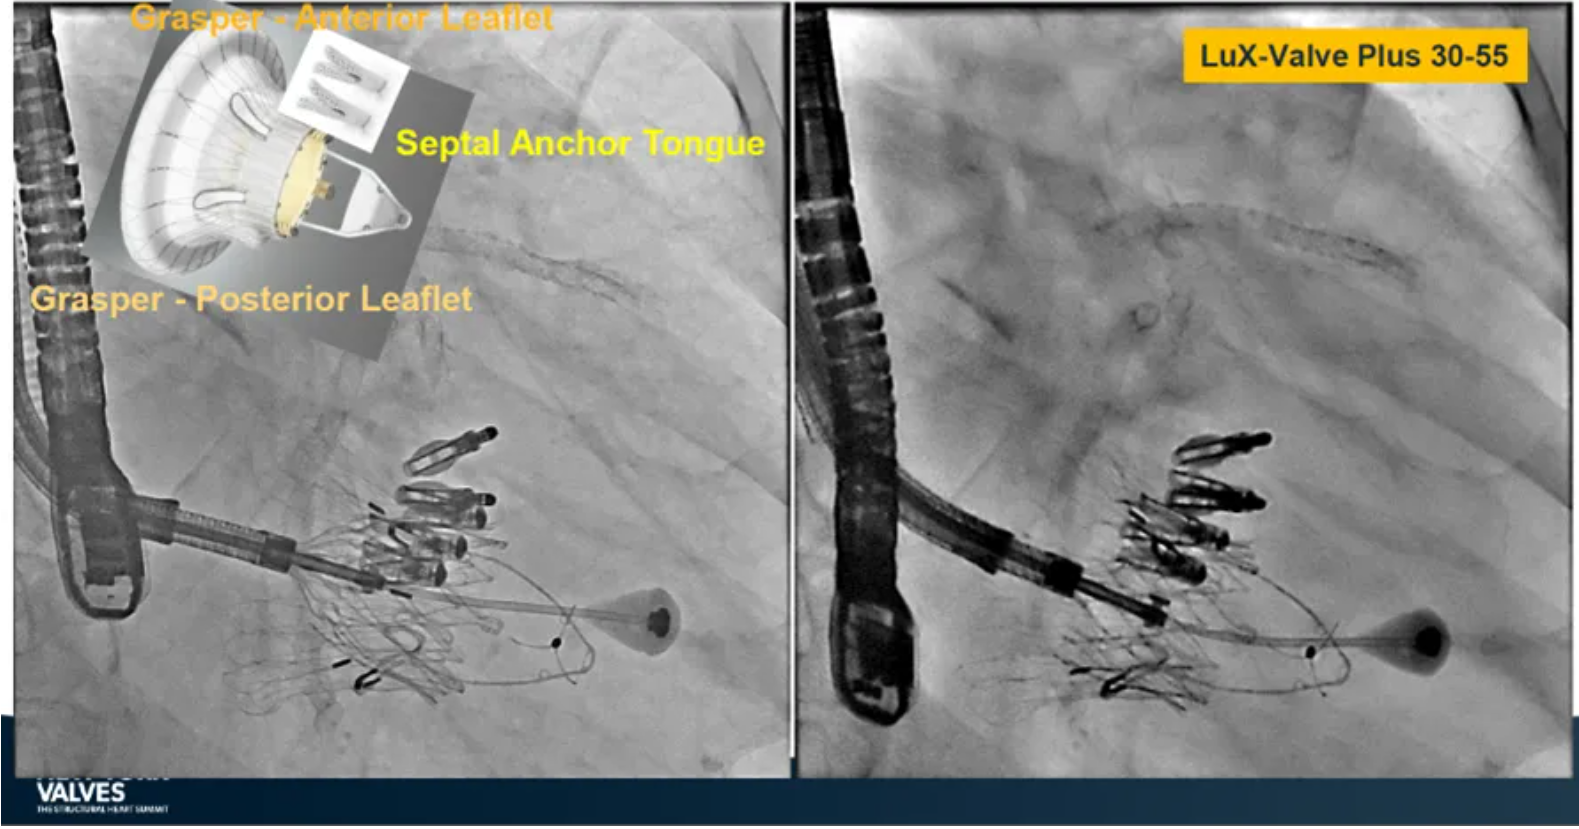

Granada教授表示,LuX-Valve Plus是一款不依賴于徑向支撐力固定的多功能TTVR器械,它的創(chuàng)新設(shè)計(室間隔錨定和瓣葉夾持件)提供了多樣的固定和穩(wěn)定技術(shù)。多中心臨床試驗研究TRAVEL II 展現(xiàn)了LuX-Valve Plus的安全性和有效性,能實現(xiàn)較短的器械操作時間,較低的復(fù)合事件發(fā)生率,并在6個月期時顯著降低三尖瓣反流等級,以及帶來心功能和生活質(zhì)量等指標上的明顯改善。

來自法國波爾多大學(xué)醫(yī)院(CHU de Bordeaux, Bordeaux, France)的Thomas Modine教授在2024紐約瓣膜會上介紹到針對目前三尖瓣反流臨床上的痛點,包括大瓣環(huán)、起搏器或者心臟除顫器ICD導(dǎo)線的影響、依賴術(shù)中影像,以及術(shù)后起搏器的植入等,LuX-Valve Plus都能夠提供良好的解決方案。他在最后總結(jié)道,LuX-Valve Plus創(chuàng)新的設(shè)計能夠有效降低術(shù)后的并發(fā)癥,例如起搏器植入率和血栓的形成。同時,TRAVEL II 研究的6個月期數(shù)據(jù)也體現(xiàn)了產(chǎn)品較短的器械操作時間,較低的復(fù)合事件發(fā)生率,顯著改善的心功能和生活質(zhì)量,以及能夠跟術(shù)前就已經(jīng)存在的起搏器導(dǎo)線兼容的優(yōu)勢。

來自中國上海復(fù)旦大學(xué)附屬中山醫(yī)院的魏來教授在2024年臺北瓣膜高峰論壇上分享了他使用LuX-Valve Plus治療三尖瓣反流的經(jīng)驗。魏來教授闡述道,隨著療法演變,目前全球市場有以LuX-Valve Plus及其他產(chǎn)品為代表的經(jīng)導(dǎo)管三尖瓣介入置換系統(tǒng),逐漸成為重度三尖瓣反流的一線治療方案。他介紹到,LuX-Valve Plus創(chuàng)新的室間隔錨定和經(jīng)頸靜脈入路的方式,能夠帶來安全穩(wěn)定的錨定效果及較短的輸送行程;其可調(diào)彎的輸送系統(tǒng)能保證同軸性,從而快速和安全地將人工瓣膜送達目標手術(shù)區(qū)域,有效降低入路周邊解剖組織并發(fā)癥及術(shù)中出血風(fēng)險。